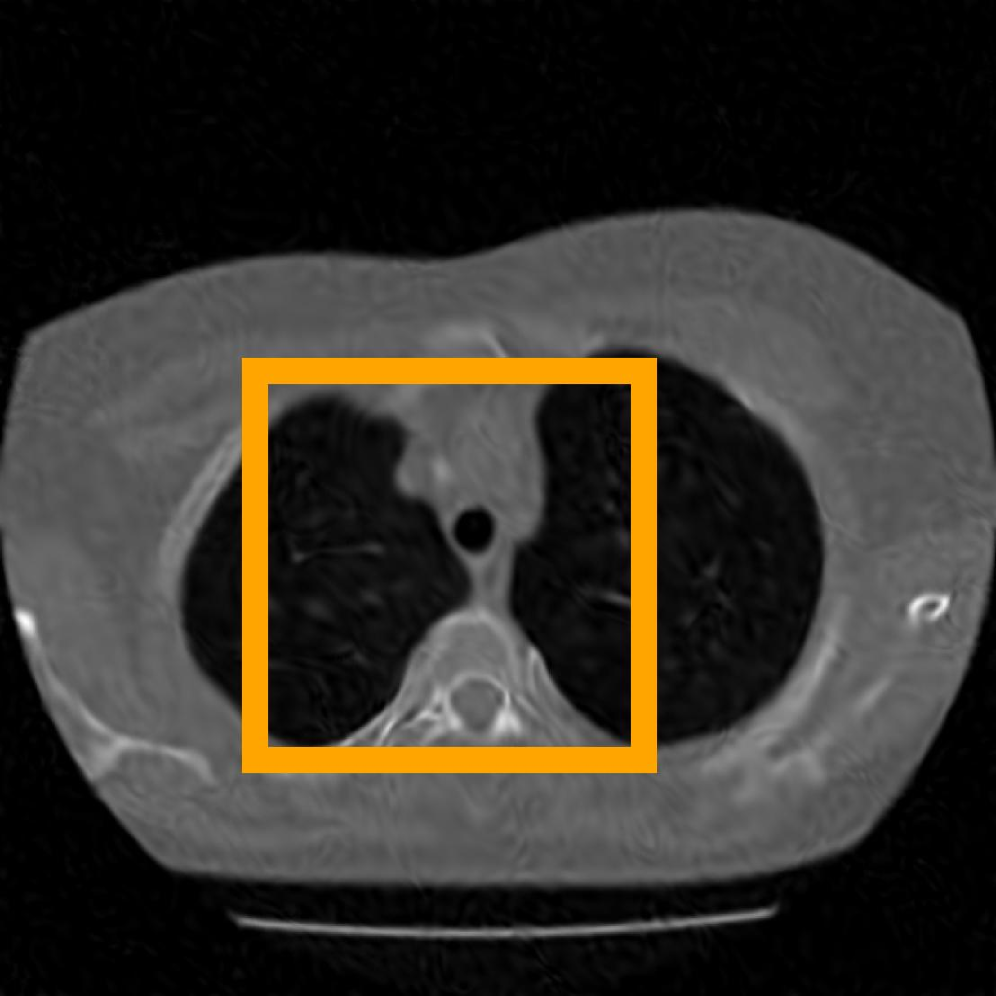

Figure 10: The visual comparison of different compression methods on a CT Heart Segmentation image.

Figure 11: Zoomed-in view of the highlighted region in Figure 10.

Figure 12: The visual comparison of different compression methods on another CT Heart Segmentation image.

Figure 13: Zoomed-in view of the highlighted region in Figure 12.

IV-B3 Visual Comparison

Figures 7 and 8 present representative examples from the CIL dataset and their zoomed-in regions, respectively. For the CT Heart Segmentation dataset, Figures 10 and 12 illustrate typical reconstruction results, while Figures 11 and 13 further enlarge local regions to compare structural details. Across both datasets, COLI preserves fine structures and global continuity well even at relatively low bpp. Specifically, on the CIL dataset, COLI attains the lowest bitrate among INR-based methods while still maintaining clear texture details. On the CT Heart dataset, COLI also operates at a low bpp within the INR family and delivers superior visual quality with improved detail fidelity and smoother structural presentation. The zoomed-in regions show fewer blocking artifacts and smoother transitions, making COLI especially suitable for large images and medical images. These visual results validate that INR-based compression can achieve efficient storage with reliable perceptual consistency, offering practical advantages for real-world large-scale image processing.